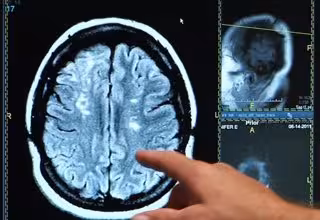

Ictus, derrame cerebral, cerebro